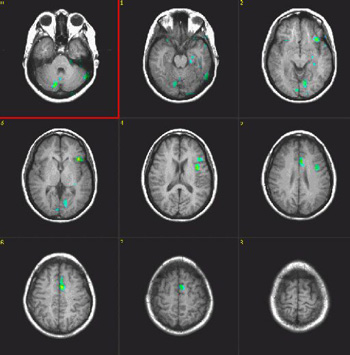

Semantic Fluency

| Subject |

Right handed, 25 year-old woman |

| Paradigm |

ON: Retrieving words within a given category

OFF: Think of a dark sky |

| Statistics |

| Statistical method |

P Value |

Z score |

| T-Test |

0.00005 |

4.2 |

|

| Images |

| Activation |

The left hemisphere shows predominant activation. The following areas were activated: Broca's, left posterior portion of middle and inferior temporal gyri (Brodman's 37), left parietal and left premotor strip. Wide activation is seen in the inferior aspect of the occipital lobes. The main activation on the right is located in the inferior aspect of the frontal lobe (Brodman's 11), a finding consistently seen in this paradigm. |